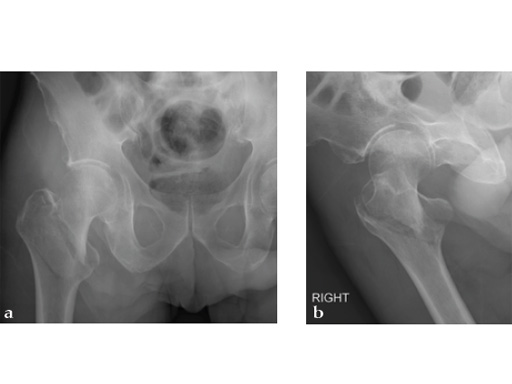

72-year-old female who sustained a closed intertrochanteric fracture in a car accident. The fracture was classified as an 31-A3-1. There were no other injuries reported.

Case provided by Cliff Turen, Macon, USA